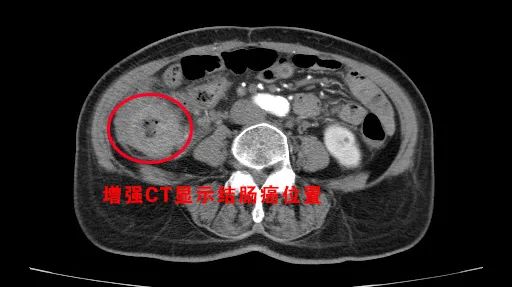

就这样李大姐在家人的陪同下,来到沈阳经济技术开发区人民医院(三级综合医院),普外科刘亮主任亲自参与会诊,结合既往检查结果,又做了增强CT,明确了李大姐的具体病情和病灶部位;刘亮主任决定为李大姐实施在ERAS快速康复理念下的腹腔镜结肠癌根治术!